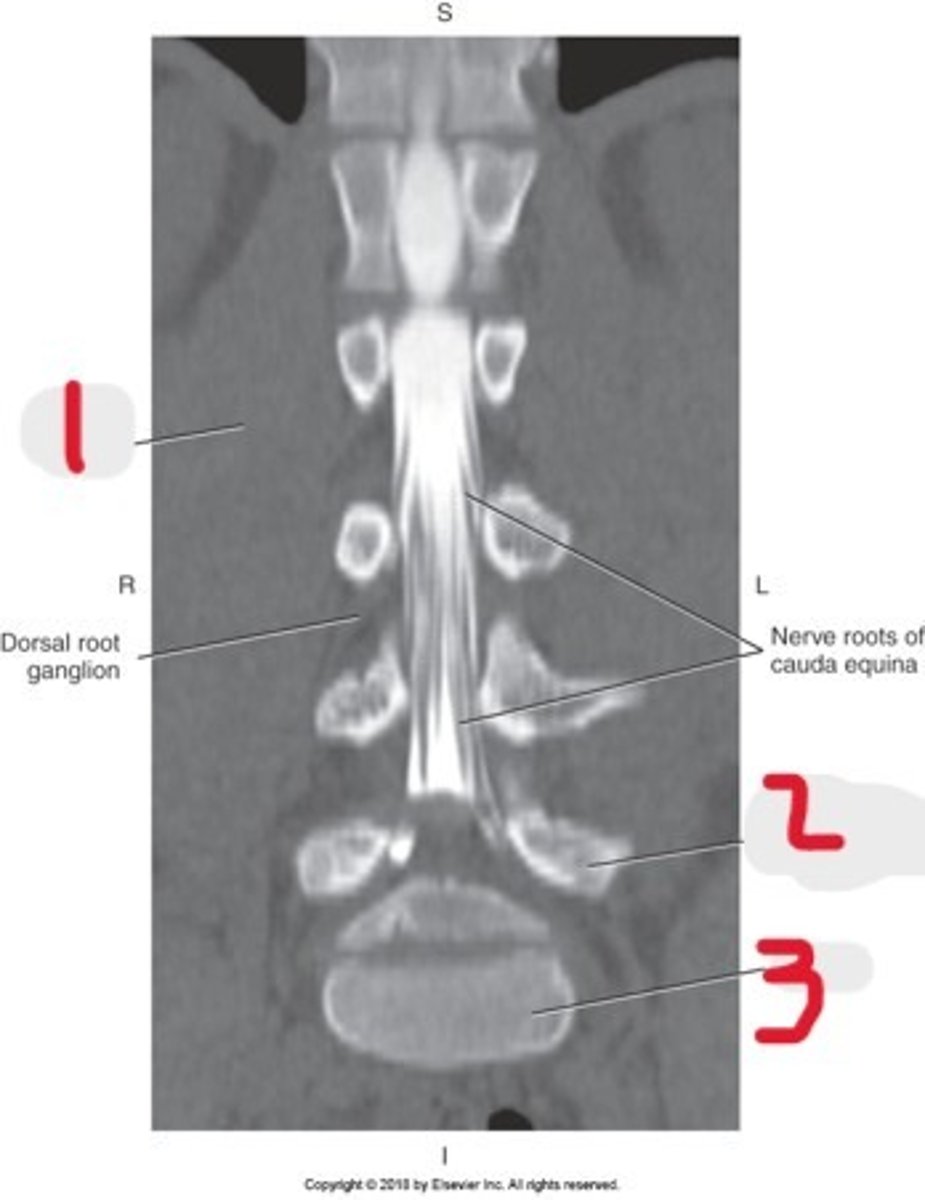

1) Conus medullaris

2) Cauda equina

3) Thecal sac

Name all numbered structures

1) Psoas muscle

2) Cauda equina

Name all numbered structures

1) Psoas muscle

2) Vertebral body

3) Cauda equina

Name all numbered structures

1) Sacrum

2) Conus medullaris

3) Cauda equina

Name all numbered structures